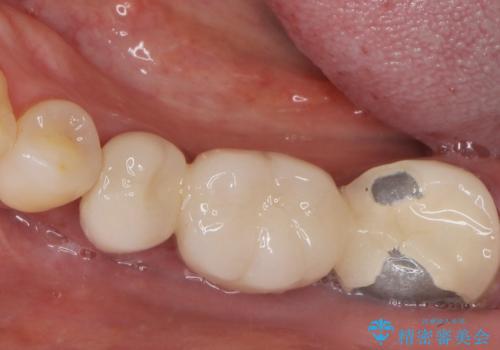

根管治療後、メタルボンドブリッジによる補綴治療を行いました。

自然な仕上がりと咬み心地に喜んで頂けました。

クラウンの種類:メタルボンドクラウン エコノミー